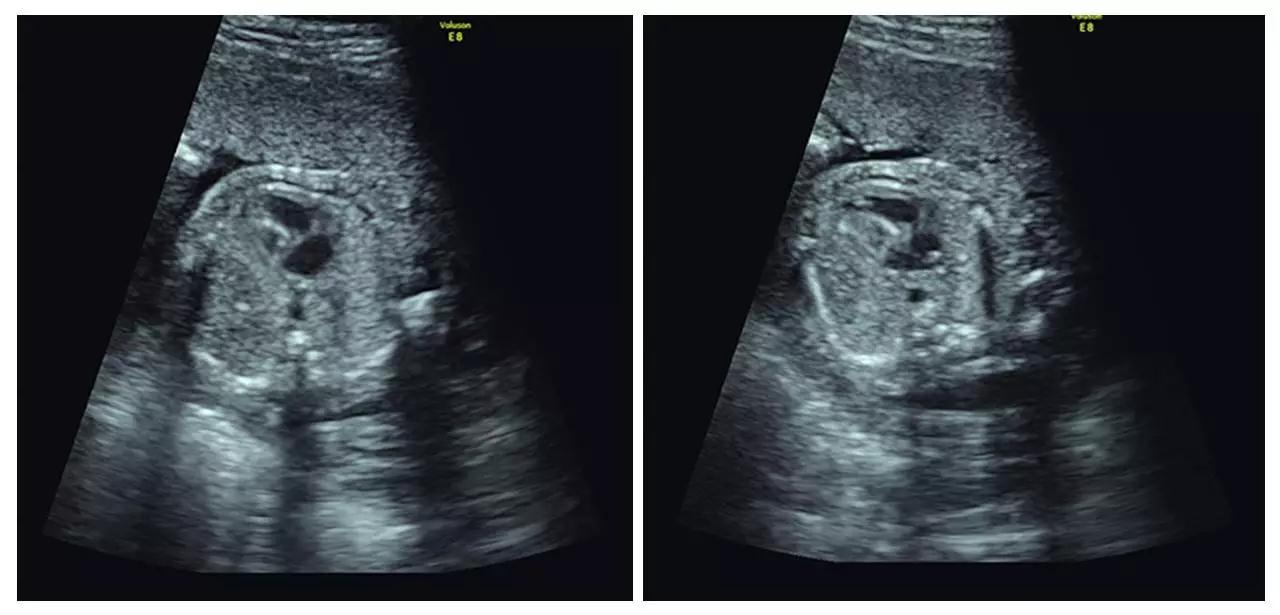

(颈后水囊瘤)

(胎儿左手未见,考虑截肢畸形)

(胎儿颅内结构异常、眼距窄、鼻结构异常...)